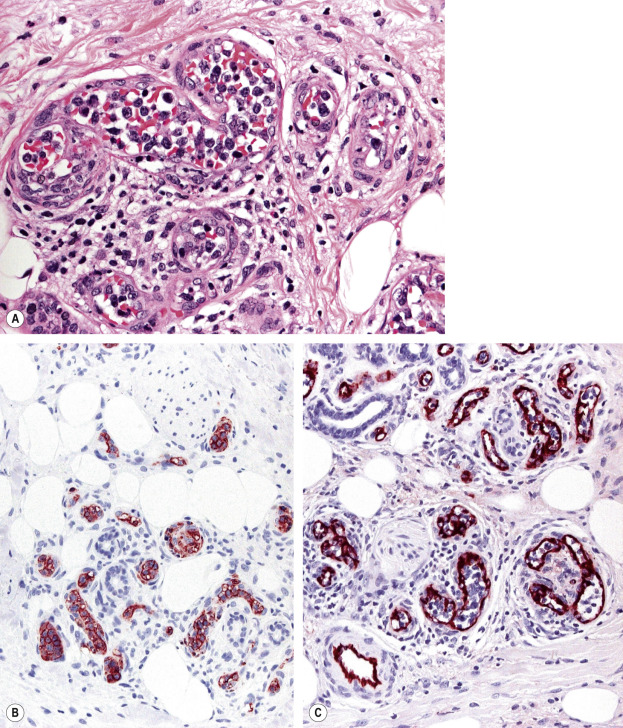

IVDLBCL is characterized by a proliferation of large atypical lymphocytes that fills dilated blood vessels within the dermis and subcutaneous tissues ( Fig. 119.14A ). The malignant cells are large with scanty cytoplasm and often have prominent nucleoli. They are positive for B-cell-associated markers ( Fig. 119.14B ) as well as for Bcl-2, MUM-1 and FOX-P1. Staining with endothelial cell-related antibodies (e.g. CD31, CD34) highlights the characteristic intravascular location of the cells ( Fig. 119.14C ). Molecular analysis shows monoclonal rearrangement of IGH . The genetic profile is similar to that observed in diffuse large B-cell lymphomas, activated B cell type.